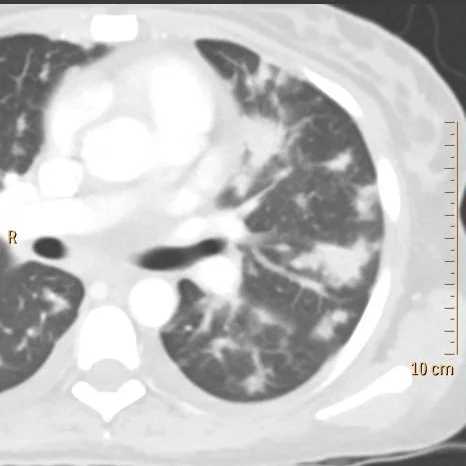

A young female immigrant presented with productive cough and fever. She had a history of previous peritoneal TB, and AIDS, and pulmonary TB was suspected with diffuse infiltrates seen on chest X-ray. CT scan of the chest performed with IV contrast showed diffuse infiltrates concerning for pneumonia.

Closer look at some of the non-confluent upper lobe infiltrates show a "flame-shaped appearance". On spectral analysis, these nodules show substantially higher iodine uptake than background lung.

Conventional CT (lung windows)

Infiltrates in left lung have "flame shaped" appearance